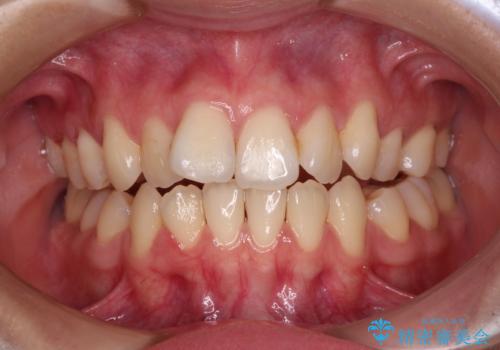

【非抜歯】ガタつきと歯軸を正して長持ちする歯へ

【モニター】前歯のデコボコをインビザラインで改善